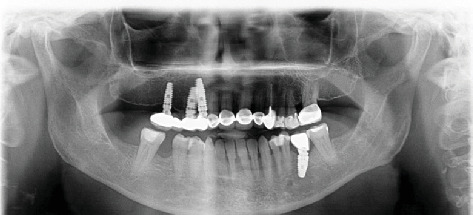

前言:种植牙科作为治疗缺牙患者康复的首选,其需求日益增长。临床医生可以在无牙空间遇到无症状的保留根碎片。本病例报告介绍了种植体晚期失败的长期预后,种植体放置11年后仍有根残余附着在固定装置上。病例报告:一名68岁女性患者在首次植入种植体11年后,因上颌右侧四单元种植体支撑桥功能相关而就诊。拔除修复体后,发现残根附着在中间支撑种植体的固定物上。种植体无意中侵占了残根碎片的中间部分,这是在拔桥时意外发现的。结论:考虑到潜在的阻碍骨整合的风险,临床医生在种植体中使用保留的根残余物时应格外注意。然而,被侵占的种植体和根碎片的骨整合是合理的,没有观察到有害的短期影响。风险-收益评估应该单独评估,因为后期失败仍然可能发生。试验注册:ClinicalTrials.gov标识符:NCT06671678。

Introduction: There is a growing demand for implant dentistry as the first choice of rehabilitation for treating patients with missing teeth. Clinicians can encounter asymptomatic retained root fragments in edentulous spaces. This case report presents the long-term prognosis of an implant resulting in late failure, with an attached root remnant to the fixture 11 years after implant placement. Case Report: A 68-year-old female patient presented to the clinic with complaints of function related to a maxillary right four-unit implant-supported bridge 11 years after the first insertion of the implants. After the removal of the restoration, a root remnant was found as adhered to the fixture of the middle supporting implant. The implant was placed encroaching upon the mesial part of the residual root fragment left unintentionally, which was discovered accidentally during the bridge removal. Conclusion: Clinicians should show ultimate attention when utilizing the retained root remnants in implant sites, considering the potential risk of hindering osseointegration. However, osseointegration of the encroached implant and root fragment is plausible, with no detrimental short-term impacts observed. A risk-benefit evaluation should be assessed individually, as late failures can still occur. Trial Registration: ClinicalTrials.gov identifier: NCT06671678.